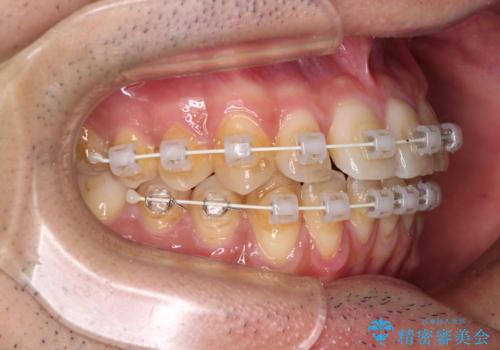

ワイヤー装置での上下前歯の部分矯正

- 上下前歯のデコボコを気にして来院された患者様です。

口元の突出感や奥歯の咬み合わせに問題がなかったため、インビザラインの廉価版パッケージを用いるか上下ワイヤー装置での部分矯正を提案しました。

インビザライン廉価版パッケージの方が価格としては安価でしたが、日々の自己管理が煩雑であるとのことで、ワイヤー装置にて矯正治療を行うこととしました。

部分矯正は咬み合わせが不安定になったり、スペースができてしまったりと、適用となる患者様は極めて限られますが、こちらの方はスムーズに治療を終えることができました。